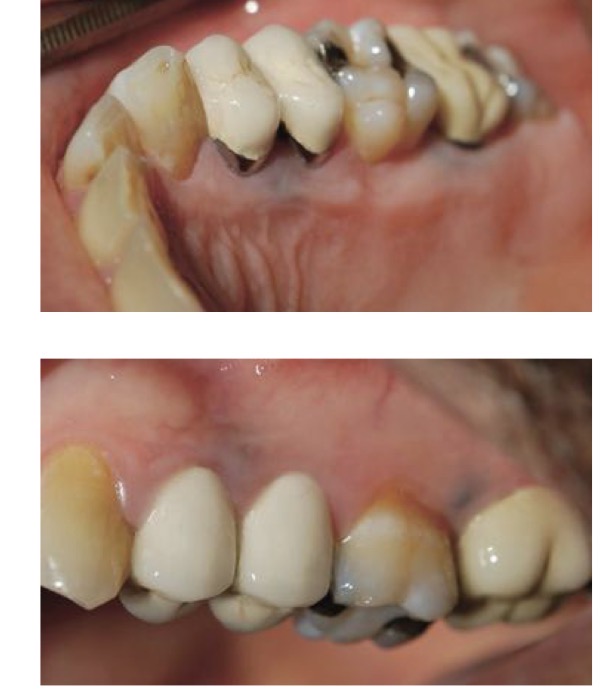

BN CÓ GAI NƯỚU TĂNG SINH, SƯNG TO, CẮNG BÓNG

SỜ DAI, KHÔNG ĐAU, KHÔNG CHẢY MÁU *

CHẨN ĐOÁN

TRIỂN DƯỠNG NƯỚU DO THUỐC PHENYTOIN